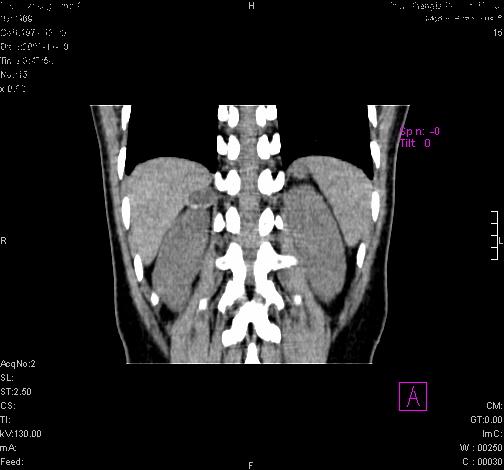

标题: CL0340:【】肾上腺囊肿,比较典型。

患者为年轻女性,查体发现右侧肾上腺囊性占位。无临床体征。

这么漂亮的图像,一看一目了然。典型的右侧肾上腺囊肿,周围有钙化。感谢搂主!

这么漂亮的图像,一看一目了然。典型的右侧肾上腺囊肿,周围有钙化。感谢搂主

右侧肾上腺囊肿,周围有钙化。